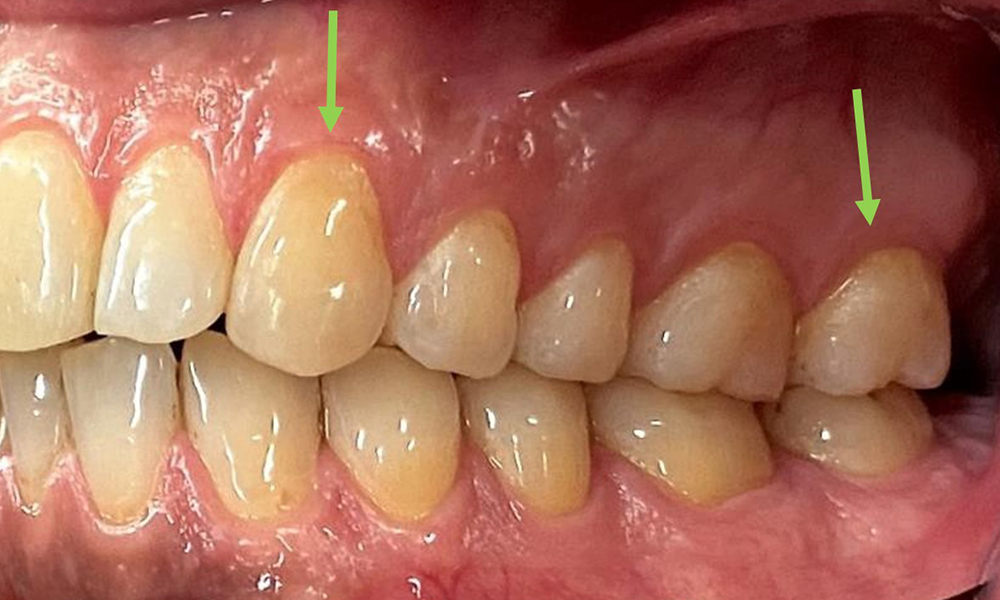

Extraoral and intraoral findings

There were no pathological extraoral findings. During intraoral examination, inspection of the frontal view revealed brownish discolouration near the keratinised gingiva and at the transition to the moveable mucosa (Fig. 2), which could be attributed to nicotine consumption. Whitish mucosal lesions were observed on the palate, particularly near the maxillary molar palatal surfaces, indicating increased keratinisation and can also be attributed to nicotine consumption. The tongue was covered with a removable white and brownish coating.

At 1 to 3 mm, the clinical probing depths were within the physiological range. Maxillary recessions of up to 1 mm were observed from 13 to 16 and 23 to 27. The BOP was 15%.